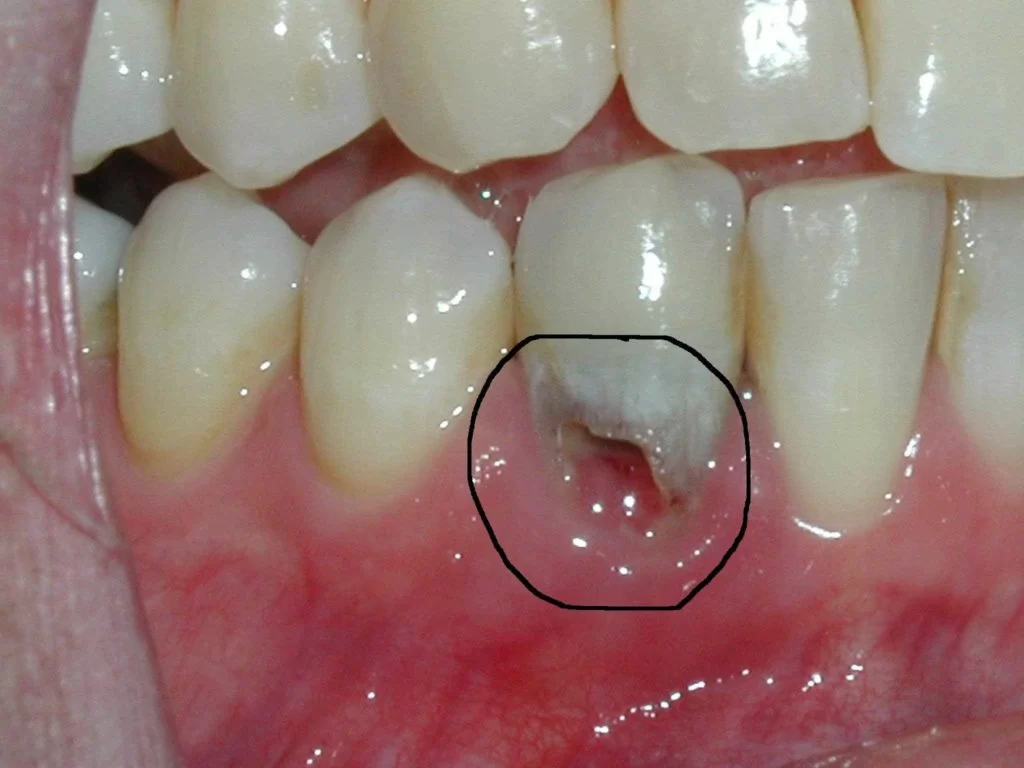

Tiêu xương chân răng

Tiêu xương răng (hay còn gọi là loãng xương) là tình trạng xương trở nên mỏng và yếu hơn bình thường. Điều này thường xảy ra khi lượng khoáng chất trong xương giảm đi hoặc khi quá trình hấp thu khoáng chất của cơ thể bị suy giảm.

Tiêu xương răng có thể gây ra nhiều vấn đề, bao gồm dễ gãy xương, đau đớn và sưng tấy. Nếu không được chữa trị kịp thời, tiêu xương răng có thể dẫn đến các vấn đề nghiêm trọng hơn như loãng xương toàn thân và các chấn thương liên quan đến xương.